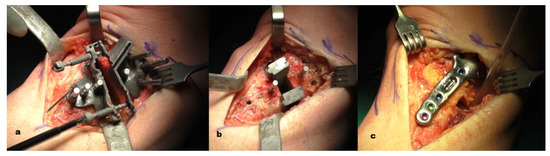

4.3. Surgical Technique